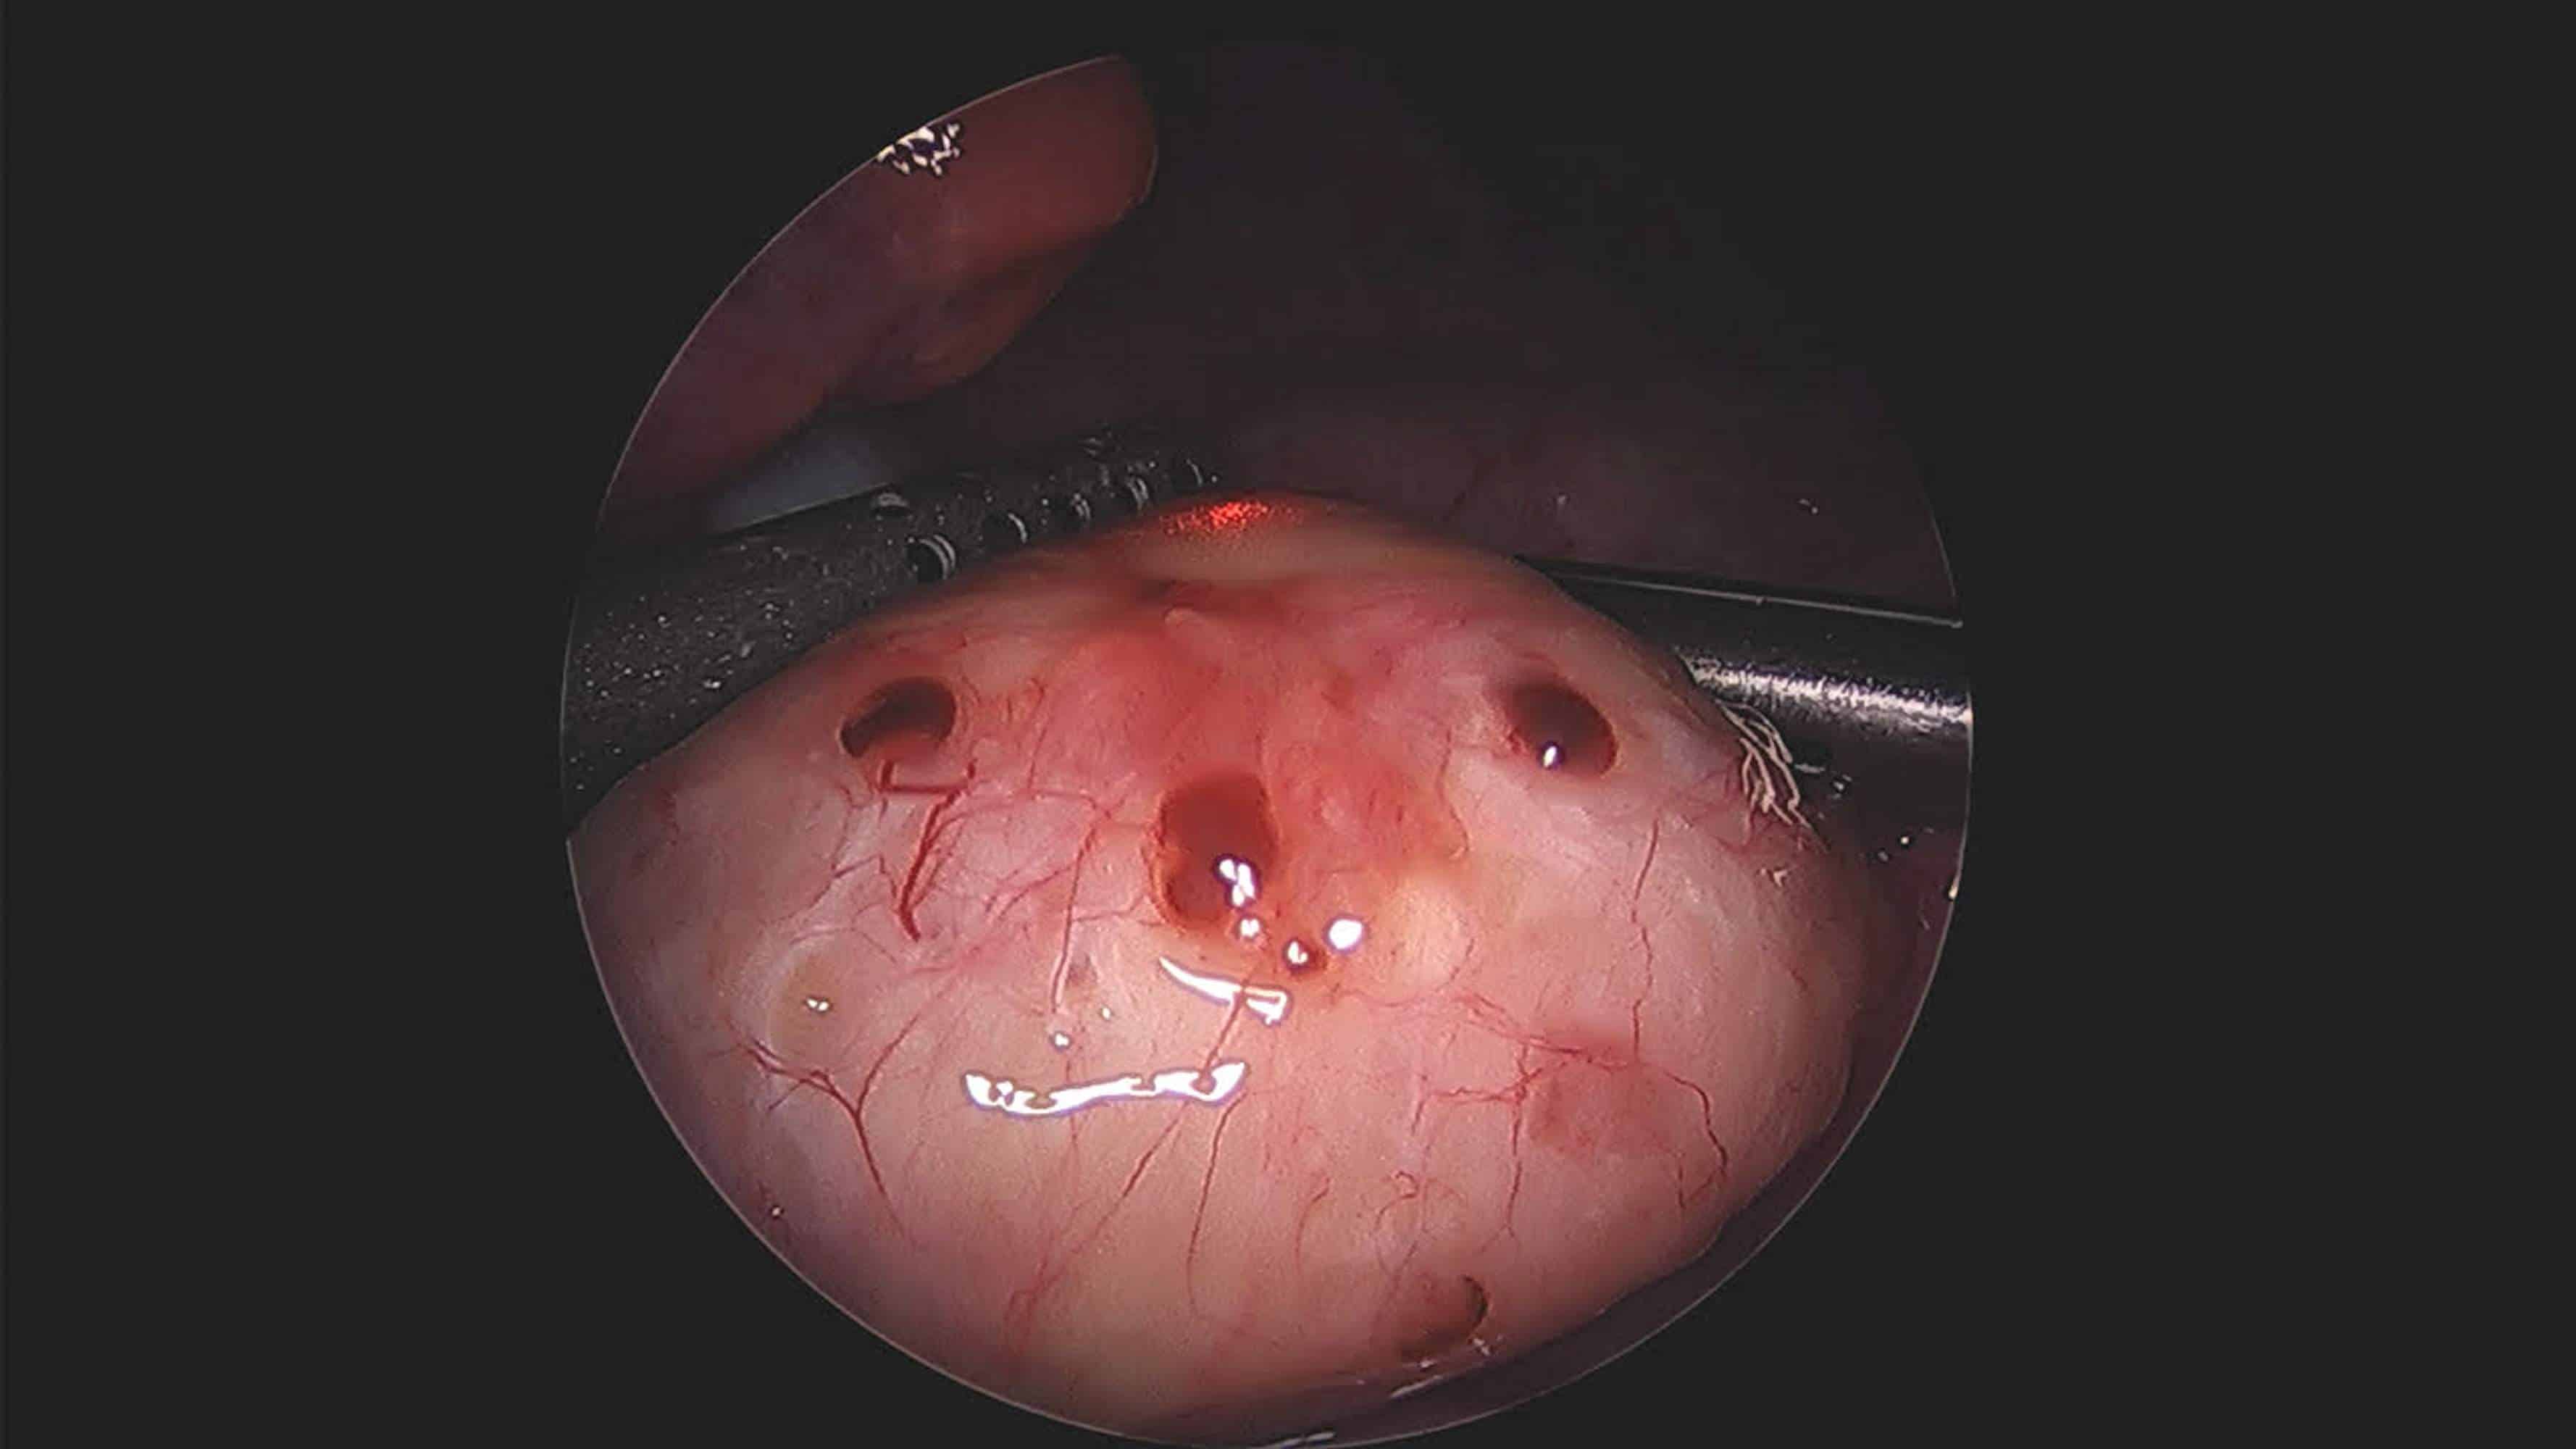

endometriosi

Endometriosi tra diagnosi in ritardo e differenze territoriali

Endometriosi, patologia ancora sotto-diagnosticata

Asp Agrigento, “Open day” di visite per fare luce sull’endometriosi

Catania, Open day contro endometriosi al Garibaldi Nesima: decine di visite gratis

Endometriosi, colpita una donna su dieci: open day al Garibaldi di Catania

Endometriosi, diagnosi con otto anni di ritardo medio